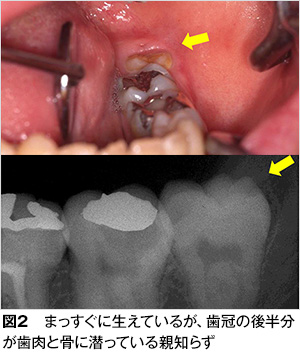

親知らずは一般的には、上あごの左右2本と下あごの左右2本の計4本ありますが、もともと親知らずの無い人や、必ずしも4本が揃っていない人など個人差があります。親知らずの生えてくる場所が不足している、あるいは萌出方向(生える方向)が通常と異なるために、埋伏(埋まった状態)していたり、傾いてきちんと生えてこないことがしばしばみられます(図2〜5)。